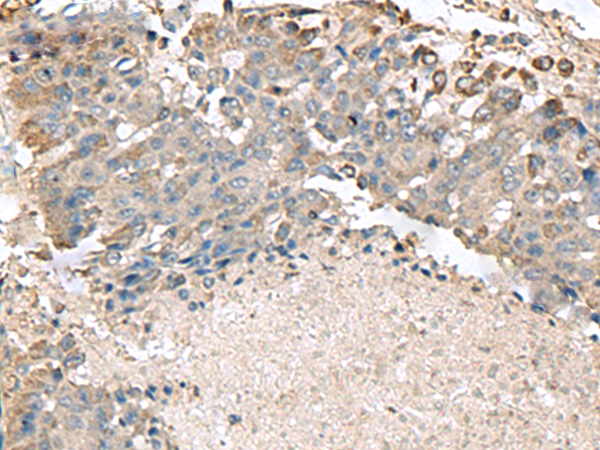

The image is immunohistochemistry of paraffin-embedded Human esophagus cancer tissue using 47428(TMEM141 Antibody) at dilution 1/70.(Original magnification: 200)

,

The image is immunohistochemistry of paraffin-embedded Human liver cancer tissue using 47428(TMEM141 Antibody) at dilution 1/70.(Original magnification: 200)